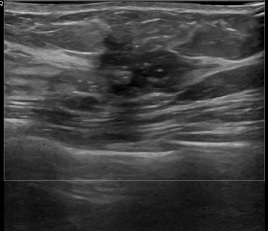

상기환자는외부검진이상소견으로 내원하신 40대 초반

여성분으로 의심스러운 좌측유방혹 조직검사 시행해 유방암 진단되었습니다.